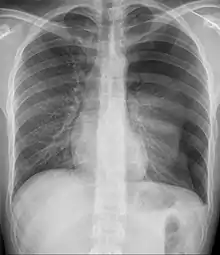

Preliminary

Since most causes of pediatric and adolescent chest pain are not considered life-threatening, parents and their children are often reassured that in the majority of cases, the cause of the pain can be determined. If the child or adolescent appears to have some dehydration, and intravenous line along with administration of saline is done. The clinician may or may not decide to perform diagnostic testing . This is especially true if the child or adolescent has symptoms of chronic pain. If an obvious cause of the chest pain is not readily apparent, testing may begin with an x-ray and an electrocardiogram . This helps the clinician to determine whether or not the cause of pain is related to pulmonary or cardiac causes.[4]